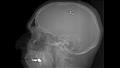

وكان الأمر معتمد على وضع شريحة حصل عليها من متجر للأدوات الكهربائية، ووضعها في الدماغ، وكانت تلك التجربة مستوحاة من فيلم Inception، معتقدًا أنها ستكون قادرة على تغيير مسار الأحلام.

ولكن تم إزالتها من الدماغ بعد مرور 5 أسابيع على الجراحة، حيث أفصح عن تجربته عبر الإنترنت، ما جعل هناك أحد استشاري المخ والأعصاب الذي انتقد فعلته الخطيرة، أن جراحات المخ والأعصاب تكون من قبل الخبراء والمؤهلين، كان من الممكن أن يفقد حياته في حالة حدوث أي مضاعفات، على سبيل المثال نزيف من الوريد القشري أو الأوعية الدموية داخل المخ، يمكن أن تصيبة بسكتة دماغية أو عجز دائم أو الموت.